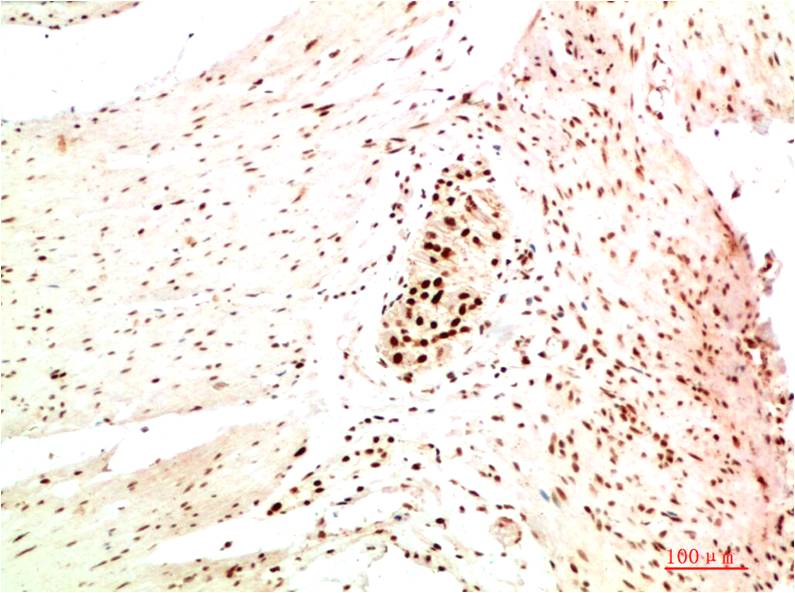

Immunohistochemistry analysis of paraffin-embedded Human Colon Carcinoma Tissue using HP1 alpha antibody.High-pressure and temperature Sodium Citrate pH 6.0 was used for antigen retrieval.

Immunohistochemical analysis of paraffin-embedded Human tonsils using HP1 alpha antibody.High-pressure and temperature Sodium Citrate pH 6.0 was used for antigen retrieval.